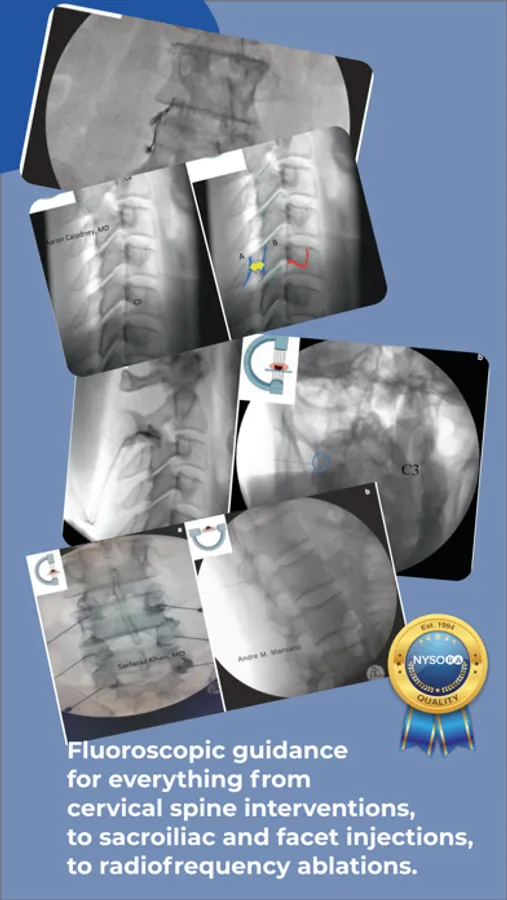

Standardized Fluoroscopy-Guided Interventional Pain Procedures

Interventional Pain App details in step-wise fluoroscopic approach evidence-based interventional pain procedures with the focus on Standards, Safety & Efficacy..

Images, illustrations, functional anatomy, and recommended interventional pain blocks and procedures.

Clear procedural steps : Paramedian Approach, AP and Contralateral Oblique Fluoroscopy Views, Fluoroscopy Technique, Target Localization – Lateral approach

Fluoroscopy-guided interventions: Interlaminar Cervical Epidural Injection, Intra Articular Cervical Facet Joint Block, C2-T1 – Posterior and Lateral Approach, Intercostal Nerve Block, Sacroiliac Joint Injection, Sacroiliac Joint Radiofrequency Ablation (Bipolar Palisade Technique), Superior Hypogastric Plexus Block – Anterior Approach, Neuroplasty (Caudal, Transgrade and Transforaminal approach), Superior Hypogastric Plexus Block – Transdiscal Approach, Splanchnic Block and Radiofrequency Ablation